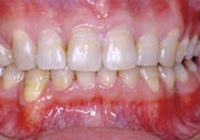

症例2:乱杭歯「歯並びが乱れている」

治療前 治療後